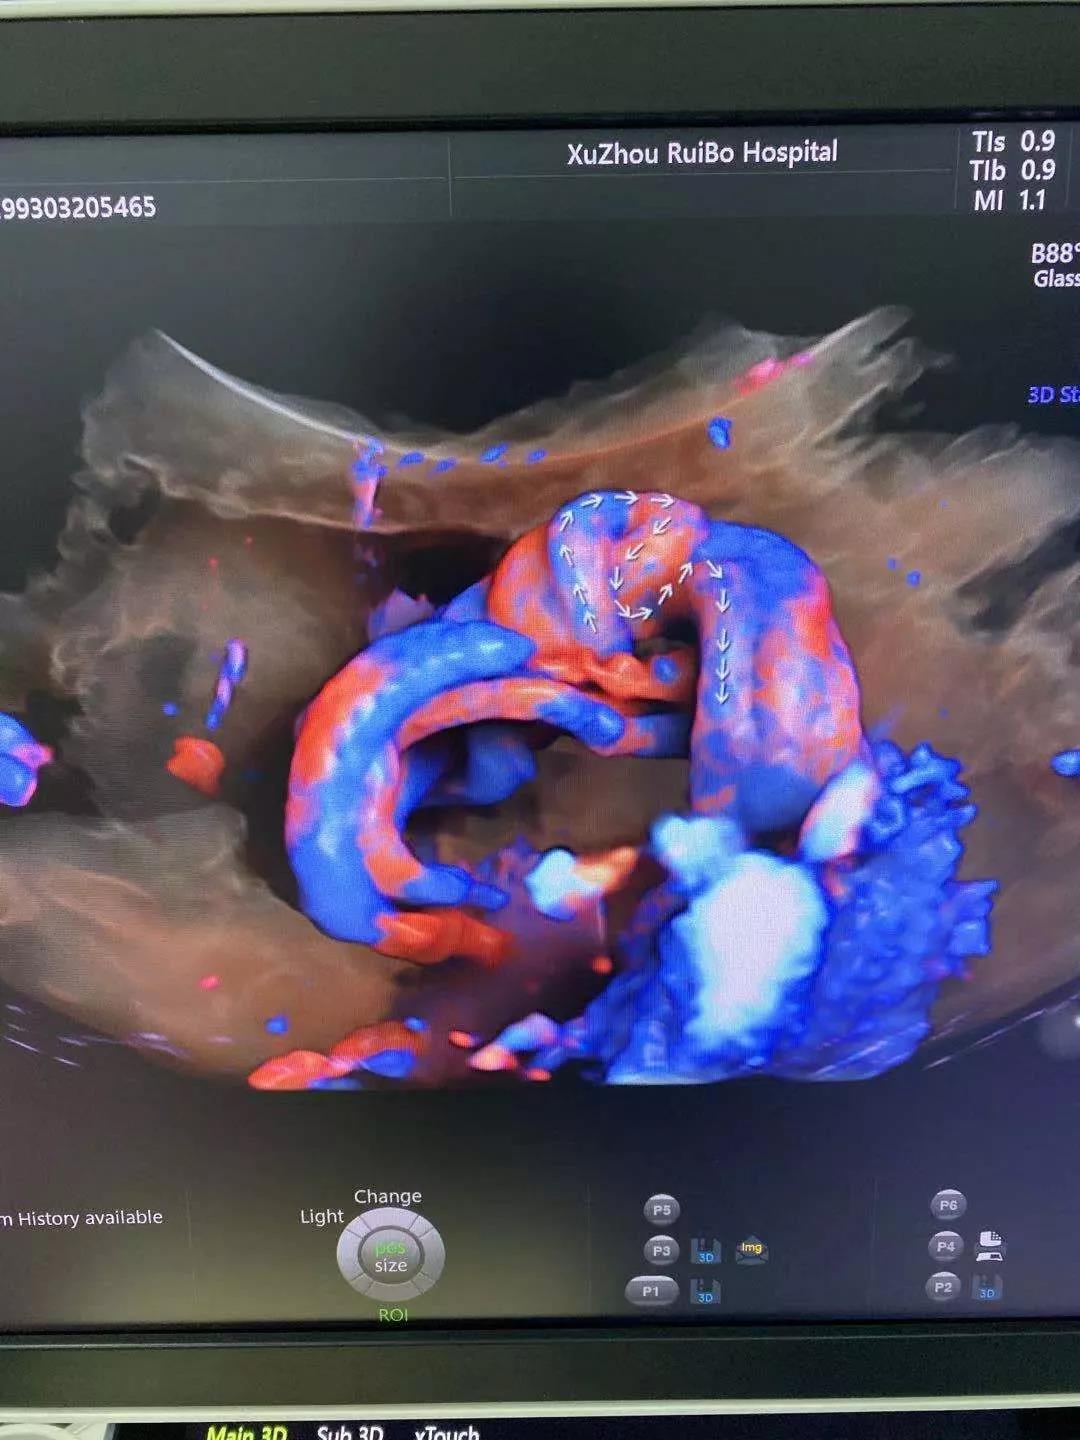

在瑞博醫(yī)院坐診

檢查出一例復雜先天性心臟病胎兒

圖:美國GE-E10四維彩超

圖:臍動脈迂曲

圖:臍帶假性打結

美國GE-E10四維彩超是專業(yè)婦產(chǎn)彩色超聲診斷儀(美國原裝進口),基于創(chuàng)新的“煊光”成像系統(tǒng)架構平臺,首次搭載煊影成像技術和煊流成像技術,配合創(chuàng)新的電子曲面矩陣四維探頭,能夠提供更多、更精準的圖像數(shù)據(jù),實現(xiàn)胎兒影像的360°動態(tài)演示,顛覆傳統(tǒng)視覺理念,讓你看得更清晰、更直觀!